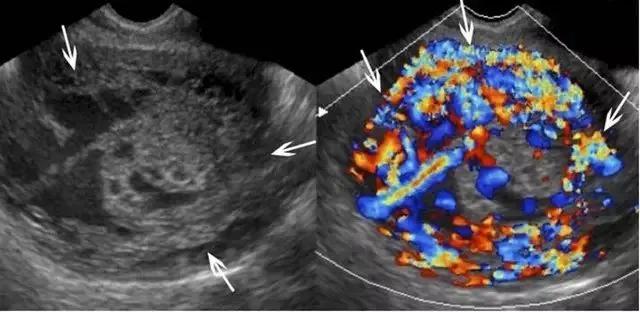

葡萄胎可分化为侵袭性葡萄胎及胎盘位置的滋养细胞肿瘤或绒癌。侵袭性葡萄胎的特点是滋养层的过度生长,并子宫肌层的广泛深度渗入;这种侵袭过程为局部性的,并未发生转移,与绒癌不同。在超声上,侵袭性葡萄胎的包块为高速、低阻性血流,其阻力指数尚低于完全性葡萄胎的阻力指数(图 18)。

图 18 为侵袭性葡萄胎:孕妇 35 岁,曾患完全性葡萄胎、并接受清宫,现在 HCG 持续升高。此图示宫腔扩张,内充满不均质的软策划,血流丰富,内膜与肌层的界限消失(箭头)。超声还可见较大的多房性卵巢囊肿(黄素囊肿,此图未显示)